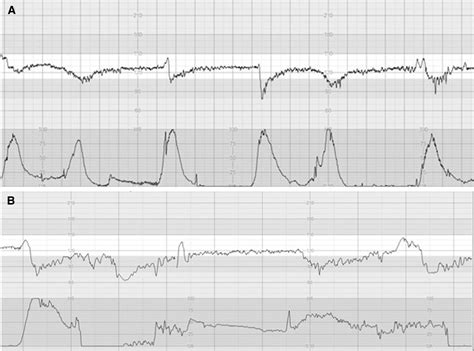

Decelerations are temporary decreases in the fetal heart rate below the baseline. They can be categorized into several types based on their shape, timing, and duration. Decelerations are often indicative of fetal distress and require careful monitoring:

• Early Decelerations: Mirror the shape of contractions and are generally benign.

• Late Decelerations: Begin after the peak of a contraction and are often associated with fetal hypoxia.

• Variable Decelerations: Vary in shape, timing, and duration and are often caused by umbilical cord compression.

• Prolonged Decelerations: Last more than 2 minutes but less than 10 minutes and can be caused by various factors, including hypoxia or medication effects.

Late and variable decelerations are particularly concerning and may require immediate intervention to ensure the fetus’s well-being.